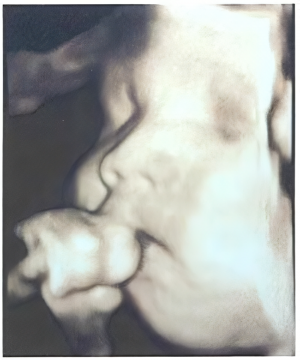

助産師による4Dエコーのご案内

赤ちゃんのかわいらしい様子をゆっくり見ることができます

ご家族の方も同席し、お話を聞いていただくこともできます

対象者

妊娠14週以降の妊婦さんとご家族

※お子さんも一緒にエコーを見ることができます

料金

2,000円(税込)

ご予約・問い合わせ:産婦人科外来

TEL0143-24-1331

【電話受付】平日 13:00~15:00

【予約枠】火~金曜日 12:00~14:30(最終受付14:00)

1枠30分の完全予約制となります